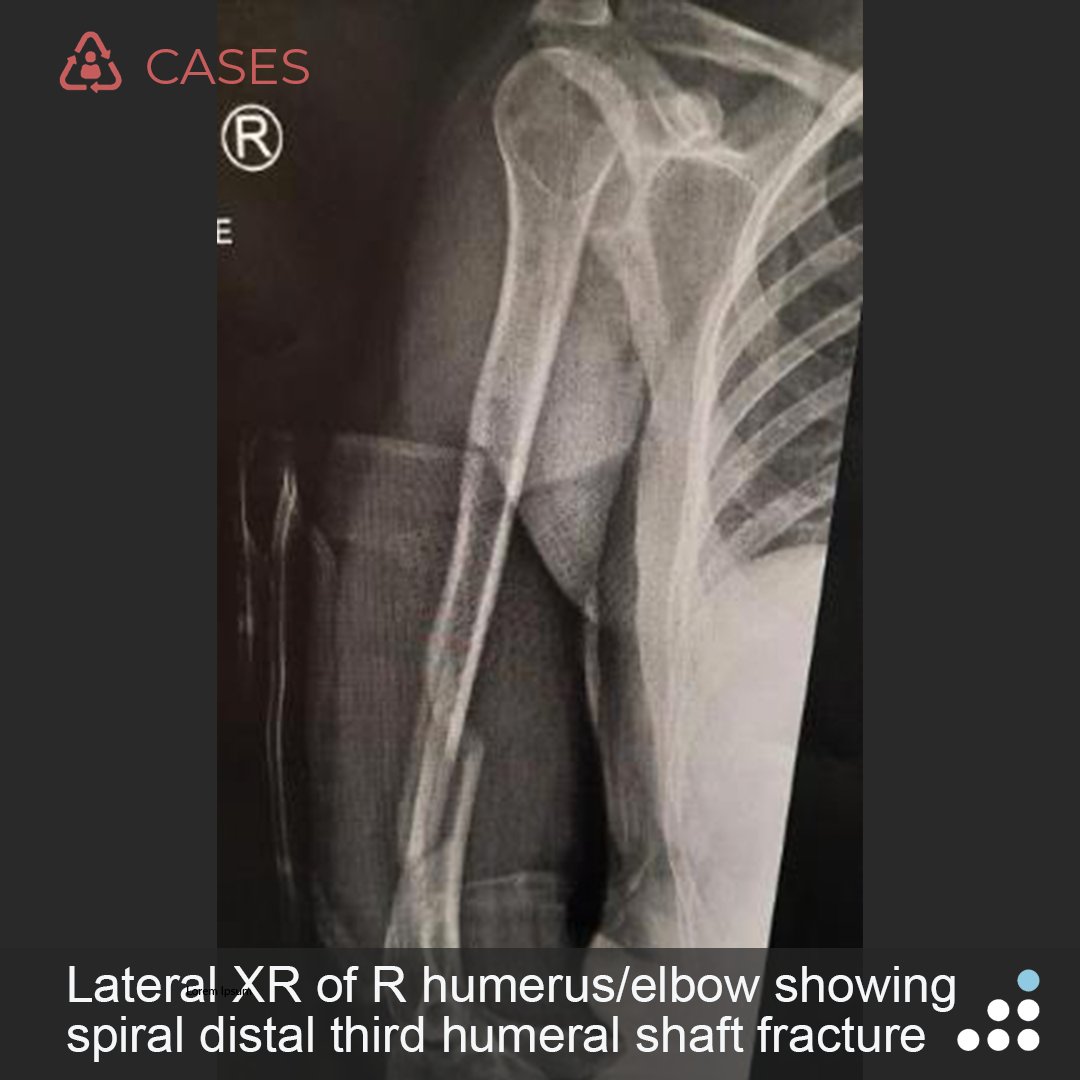

@orthobullets @KPSCALnews @rkh_md @DrMarecek @DeformityDoc @jamesablairMD @FractureDoc @stevemchale @traumaticum @DrFraneNicholas I am concerned about the +Fleck/flake sign. Get MRI or ultrasound to rule out a triceps rupture. If torn, I would perform ORIF and Triceps repair, after restoring the underlying metabolic issues. If the triceps is not torn, then would treat non-operatively.